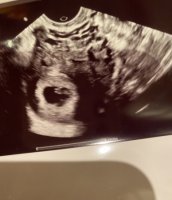

Åja, bare 6-7 ja...det var trist. Men fosteret og morkake flytter jo ikke på seg på de 14 dagene eller? Hmm, ble forvirret jeg nå. Men stemmer det at plasseringen hos meg tilsier gutt?Tror Uke 9 er for sent å bruke ramzi.. skal brukes i uke 6-7 helst